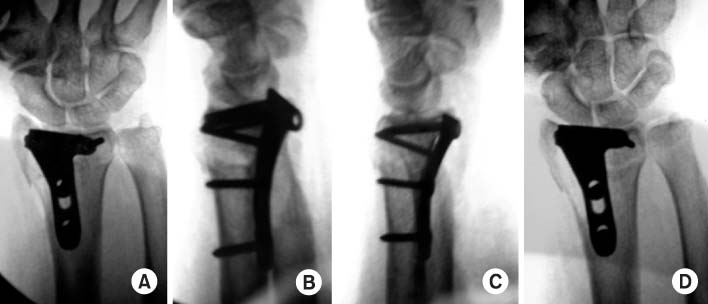

Fig. 11

(A) On anteroposterior view, plate and screws look like to violate the joint line.

(B) But they don't violate the joint on tilt view.

(C) At lateral view, it is not sure that the plate and scres involve the joint line.

(D) It can be confirmed that they don't violate the joint at radial tilt lateral view.

Fig. 11 (A) On anteroposterior view, plate and screws look like to violate the joint line. (B) But they don't violate the joint on tilt view. (C) At lateral view, it is not sure that the plate and scres involve the joint line. (D) It can be confirmed that they don't violate the joint at radial tilt lateral view.